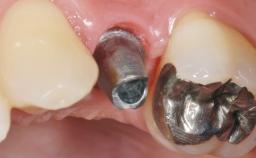

A 51-year-old female patient presented with a chief complaint of occlusal pain at tooth 24 and had been referred to our clinic for consultation and treatment. The patient had no history of any systemic disorder that may have affected the treatment outcome, and she was a non-smoker. Tooth 24 had been endodontically treated and restored with a crown at another clinic due to caries ten years before. The pre-treatment radiograph revealed a root fracture of tooth 24 with significant bone resorption. The pocket probing depth was 8 mm. The tooth had to be extracted. During the minimally traumatic extraction of tooth 24, a dehiscence was found on the buccal wall of the extraction socket. In response to the patient’s wish for a comprehensive treatment of the entire jaw,a suitable treatment plan was developed.